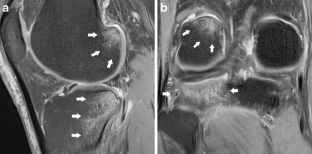

Subchondral impaction fractures of the non-weight-bearing portion of the lateral femoral condyle

Sixteen cases of intra-articular impaction fractures in a posterior, non-weight-bearing area of the lateral femoral condyle were diagnosed in patients with a mean age of 40. Eight were associated with recreational sports activities and 4 with repeated kneeling. There were no fractures documented in the non-weight-bearing aspect of the medial femoral condyles. Proposed underlying mechanisms for development of this type of fracture are presented.

Awareness, along with a high level of suspicion, that non-specific knee pain, especially in patients involved in athletic activities, could be due to intra-articular impaction fractures of the non-weight-bearing posterior aspect of the lateral femoral condyle is essential and MRI is the mainstay of diagnosis.

Fig. 1